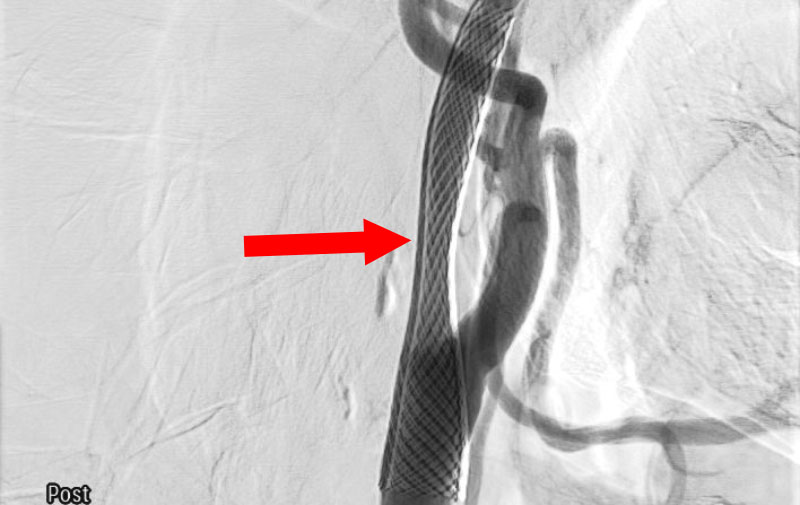

脳動静脈奇形

20代

愛知県の病院

No.1570 手術前

No.1570 手術中

No.1570 手術後